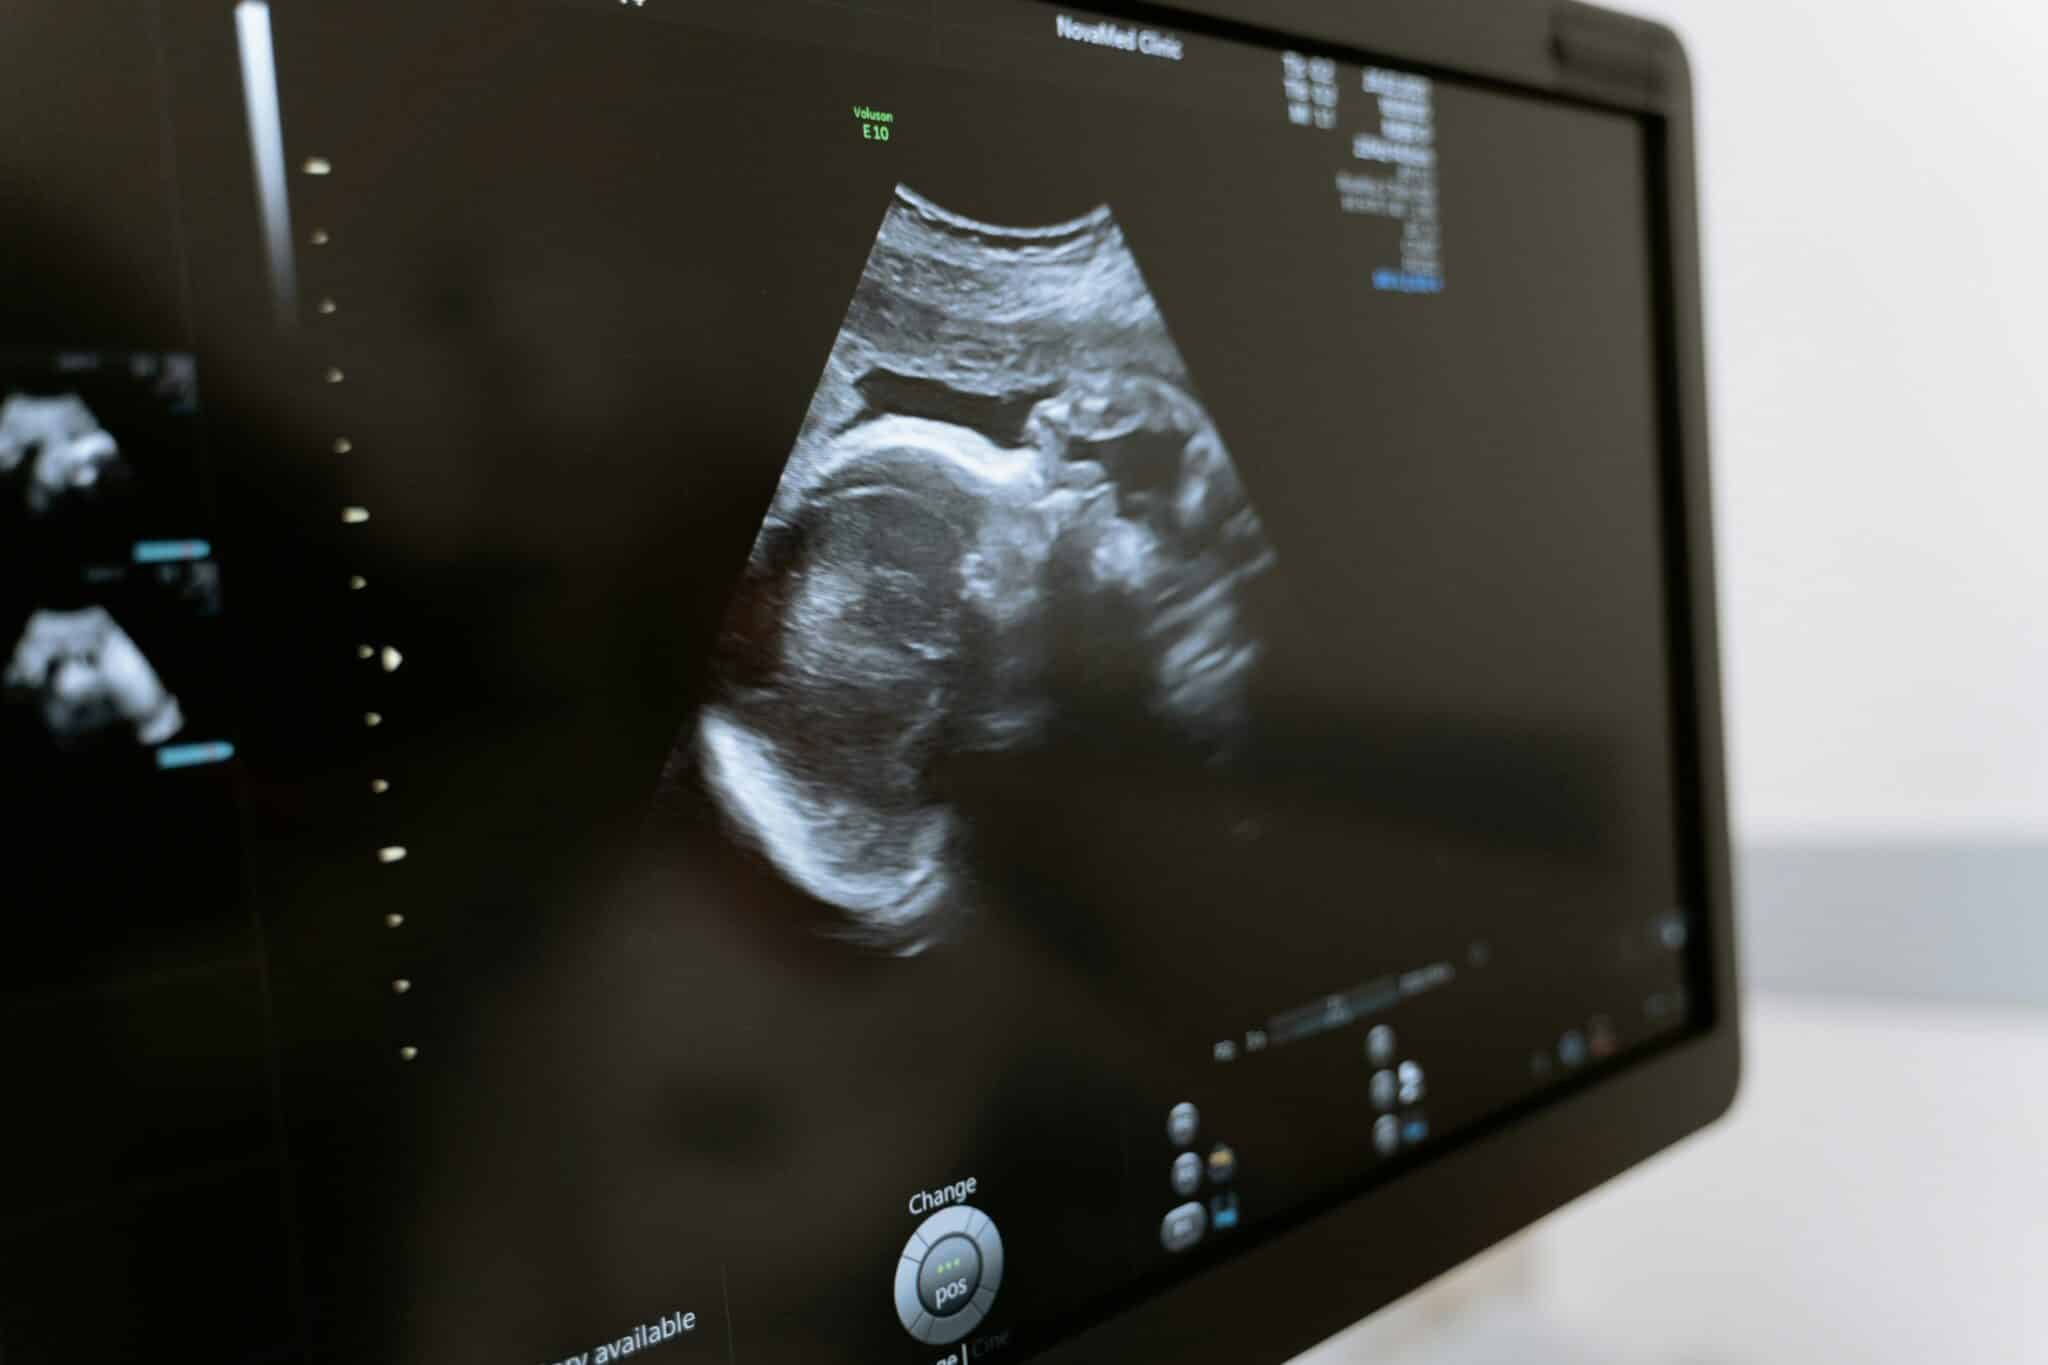

Внутрішньоматкова інсемінація (ВМІ) – це процедура, яка поєднує точність медичних технологій і турботу про процес зачаття. Її можна проводити у природному циклі, коли лікар за допомогою УЗД відстежує дозрівання фолікула і визначає момент овуляції, а також після застосування стимуляції, коли для дозрівання яйцеклітини застосовують легку гормональну підтримку. Такий підхід допомагає точно визначити оптимальний день для проведення інсемінації та підвищити шанси на успіх.